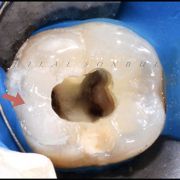

Restoring root canal treated tooth... A Conservative approach!

Based on evidence, all posterior teeth should be restored with cuspal coverage after root canal treatment. However, most of these teeth are badly destructed due to caries or large existent restoration. The key of success is to preserve the remaining tooth structure and restore the tooth conservatively. Dr khalid Merdad and I worked simultaneously to accomplish this task.